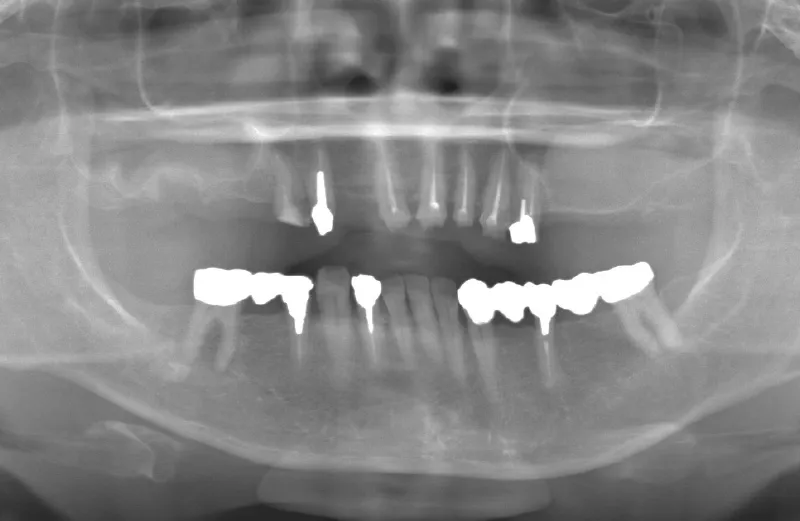

メガジェンオペの症例紹介02

治療前

治療後

| 主訴 | 左上の一番奥歯は他院にてマイクロスコープで治療してもらったが、根の状態が万全ではないのでブリッジでは治療しない方が良いと言われた。 なので左上の歯がないところにインプラントをして欲しい。 |

| 治療期間 | 2ヶ月で仮歯が入り、 3ヶ月で最終補綴物が入って終了。 |

| 費用 | 約550,000円 |

| 治療内容 | エクストラワイドショートインプラントを埋入し、上顎洞を移植材を用いずに挙上しインプラントを埋入した。約2ヶ月で仮歯を装着し、様々な機能面に問題がないことを確認し3ヶ月で最終補綴物を装着して終了した。 |

| 治療のリスク | インプラント埋入オペ時に術者が上顎洞内にインプラントを迷入させる可能性がある。これは術者が技術的に熟練していれば防ぐことが可能。 |